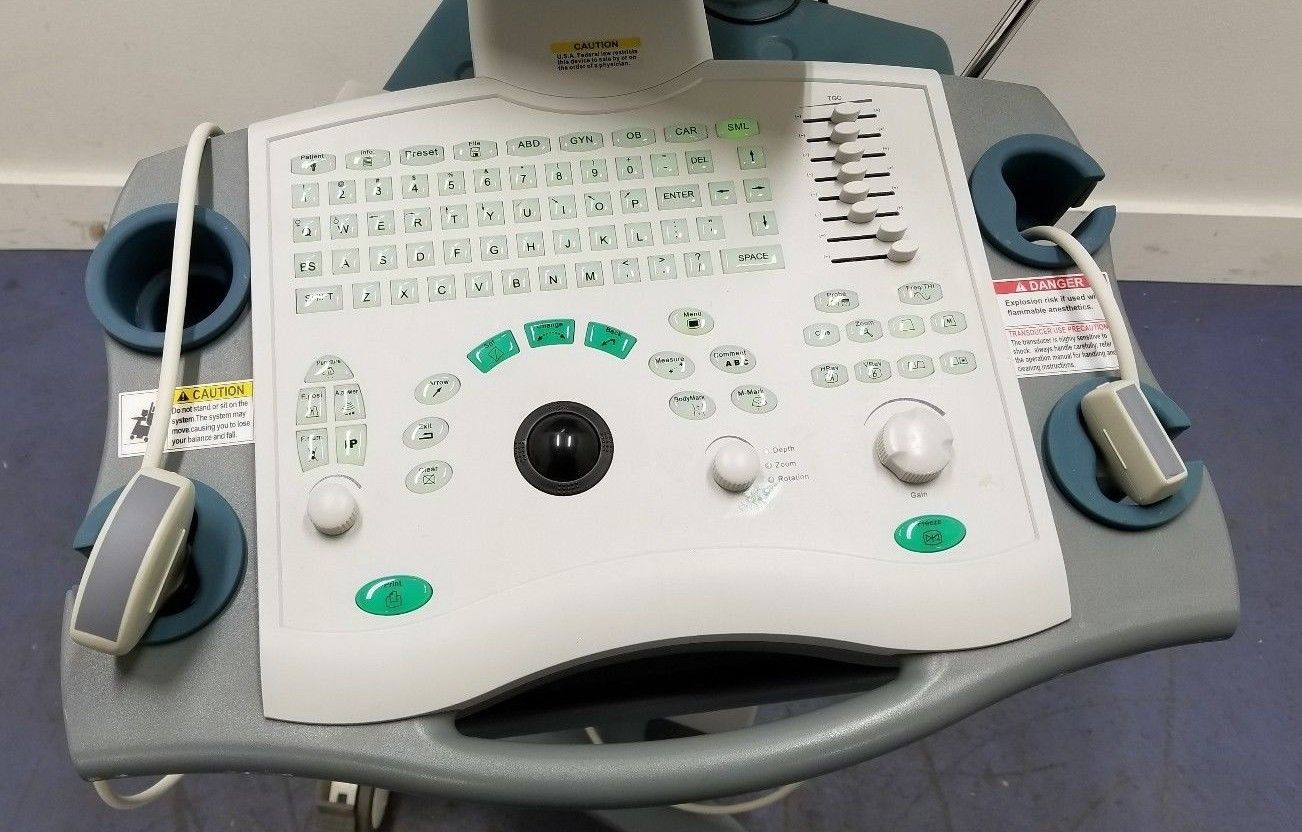

DIAGNOSTIC ULTRASOUND MACHINES FOR SALE

Mindray DigiPrince DP-6600 Ultrasound Machine with Transducer

Sale price$ 10,492.00

Regular price$ 11,192.00

Save $ 350.00

DIAGNOSTIC ULTRASOUND MACHINES FOR SALE

Mindray DP-6600 Digital Portable Ultrasound with Linear Probe Transducer

Sale price$ 2,550.00

Regular price$ 2,720.00

DIAGNOSTIC ULTRASOUND MACHINES FOR SALE

MINDRAY DP-6600 ULTRASOUND SYSTEM + 2 TRANSDUCER

Sale price$ 8,628.99

Save $ 550.00